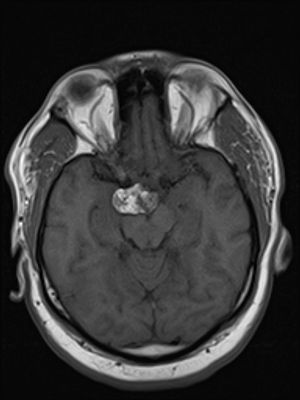

Image IQ: 46-year-old Male with Headache

ByLaura Flisnik, MD,Erini Makariou, MD

46-year-old male presents with headache.